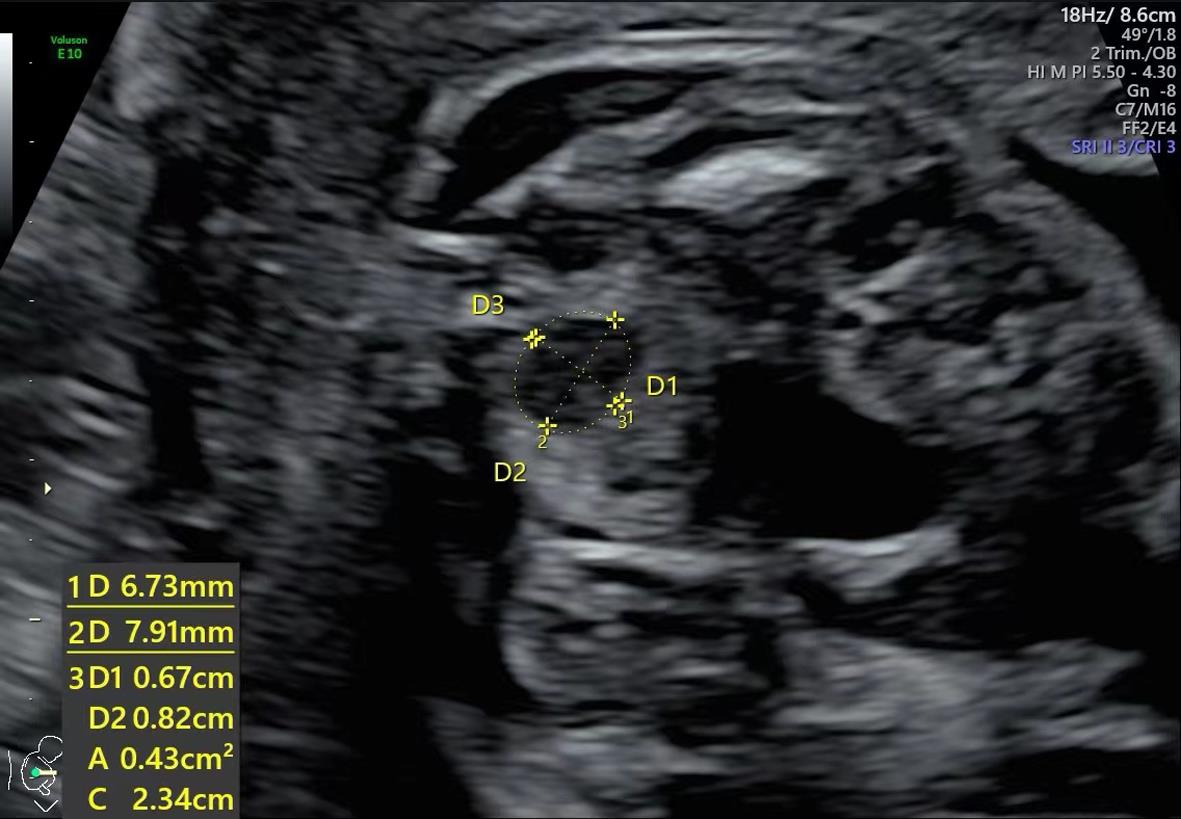

Yuqi ZHANG,Kesong ZHOU,Shiquan ZHANG,Lei TANG,Enxiu XIE,Hongquan LIAO,Tao. YANG. Correlation of fetal rectal ampulla abdominal diameter with gestational age and establishment of reference values in low⁃risk fetuses at 18 ~ 40 weeks of pregnancy[J]. The Journal of Practical Medicine, 2025, 41(6): 882-888.

Percentile reference values for rectal ampulla size parameters of low-risk fetuses at 18 ~ 40 weeks gestation"

孕周 | 样本量 | 直肠壶腹部前后径/cm | 直肠壶腹部左右径/cm | 直肠壶腹部面积/mm2 | ||||||||||||||

---|---|---|---|---|---|---|---|---|---|---|---|---|---|---|---|---|---|---|

P5 | P10 | P50 | P90 | P95 | P5 | P10 | P50 | P90 | P95 | P5 | P10 | P50 | P90 | P95 | ||||

18 | 40 | 0.231 | 0.241 | 0.310 | 0.540 | 0.656 | 0.271 | 0.281 | 0.385 | 0.668 | 0.710 | 0.061 | 0.070 | 0.100 | 0.302 | 0.388 | ||

19 | 41 | 0.331 | 0.350 | 0.400 | 0.466 | 0.479 | 0.342 | 0.370 | 0.420 | 0.478 | 0.526 | 0.121 | 0.152 | 0.180 | 0.238 | 0.277 | ||

20 | 31 | 0.316 | 0.330 | 0.380 | 0.696 | 0.722 | 0.356 | 0.360 | 0.420 | 0.618 | 0.650 | 0.110 | 0.120 | 0.140 | 0.420 | 0.526 | ||

21 | 31 | 0.396 | 0.420 | 0.470 | 0.540 | 0.560 | 0.486 | 0.490 | 0.530 | 0.568 | 0.608 | 0.176 | 0.182 | 0.220 | 0.280 | 0.330 | ||

22 | 109 | 0.415 | 0.440 | 0.550 | 0.660 | 0.680 | 0.500 | 0.510 | 0.680 | 0.820 | 0.875 | 0.190 | 0.200 | 0.310 | 0.420 | 0.480 | ||

23 | 214 | 0.340 | 0.380 | 0.520 | 0.690 | 0.740 | 0.568 | 0.610 | 0.740 | 0.900 | 0.953 | 0.208 | 0.240 | 0.350 | 0.500 | 0.523 | ||

24 | 133 | 0.354 | 0.394 | 0.550 | 0.740 | 0.792 | 0.598 | 0.634 | 0.770 | 0.906 | 0.963 | 0.237 | 0.254 | 0.370 | 0.566 | 0.600 | ||

25 | 44 | 0.383 | 0.420 | 0.625 | 0.770 | 0.780 | 0.625 | 0.695 | 0.850 | 0.980 | 1.100 | 0.310 | 0.320 | 0.480 | 0.600 | 0.628 | ||

26 | 41 | 0.524 | 0.568 | 0.790 | 0.880 | 0.916 | 0.870 | 0.880 | 0.950 | 1.256 | 1.387 | 0.531 | 0.542 | 0.650 | 0.730 | 0.919 | ||

27 | 31 | 0.792 | 0.900 | 1.050 | 1.118 | 1.142 | 0.980 | 0.982 | 1.160 | 1.218 | 1.254 | 0.852 | 0.896 | 1.020 | 1.128 | 1.134 | ||

28 | 31 | 0.884 | 0.982 | 1.070 | 1.258 | 1.308 | 1.052 | 1.090 | 1.180 | 1.298 | 1.362 | 0.772 | 0.910 | 1.020 | 1.224 | 1.584 | ||

29 | 31 | 1.036 | 1.050 | 1.090 | 1.226 | 1.262 | 1.072 | 1.172 | 1.260 | 1.364 | 1.394 | 1.050 | 1.090 | 1.130 | 1.266 | 1.292 | ||

30 | 31 | 0.722 | 0.750 | 1.090 | 1.190 | 1.220 | 0.762 | 0.822 | 1.210 | 1.260 | 1.320 | 0.668 | 0.732 | 1.070 | 1.214 | 1.440 | ||

31 | 31 | 0.976 | 1.102 | 1.190 | 1.274 | 1.312 | 1.002 | 1.116 | 1.310 | 1.388 | 1.432 | 0.982 | 1.098 | 1.190 | 1.322 | 1.350 | ||

32 | 23 | 0.904 | 1.000 | 1.170 | 1.332 | 1.404 | 1.022 | 1.078 | 1.230 | 1.444 | 1.476 | 0.842 | 0.986 | 1.140 | 1.530 | 1.686 | ||

33 | 41 | 0.903 | 1.152 | 1.500 | 1.674 | 1.753 | 1.141 | 1.200 | 1.600 | 1.748 | 1.796 | 1.006 | 1.212 | 2.000 | 2.418 | 2.494 | ||

34 | 31 | 0.948 | 1.052 | 1.390 | 1.500 | 1.628 | 0.966 | 1.246 | 1.500 | 1.590 | 1.644 | 0.840 | 1.170 | 1.380 | 2.180 | 2.352 | ||

35 | 21 | 0.834 | 1.010 | 1.460 | 1.690 | 1.726 | 1.411 | 1.440 | 1.680 | 1.856 | 1.870 | 1.402 | 1.440 | 1.650 | 2.382 | 2.985 | ||

36 | 31 | 0.936 | 1.018 | 1.390 | 1.624 | 1.654 | 0.790 | 0.868 | 1.610 | 1.758 | 1.860 | 0.630 | 0.658 | 1.620 | 2.386 | 2.572 | ||

37 | 41 | 0.962 | 1.100 | 1.510 | 1.698 | 1.748 | 1.478 | 1.582 | 1.700 | 1.830 | 1.946 | 1.432 | 1.570 | 1.870 | 2.600 | 2.719 | ||

38 | 31 | 1.400 | 1.494 | 1.720 | 1.975 | 2.040 | 1.582 | 1.676 | 1.850 | 2.024 | 2.076 | 2.012 | 2.082 | 2.550 | 3.274 | 3.406 | ||

39 | 21 | 1.563 | 1.596 | 1.900 | 2.036 | 2.076 | 1.731 | 1.760 | 1.960 | 2.106 | 2.164 | 1.881 | 1.892 | 2.580 | 3.258 | 3.604 | ||

40 | 24 | 1.425 | 1.615 | 1.970 | 2.030 | 2.053 | 1.838 | 1.865 | 1.990 | 2.090 | 2.123 | 1.878 | 1.900 | 2.030 | 2.625 | 2.798 |